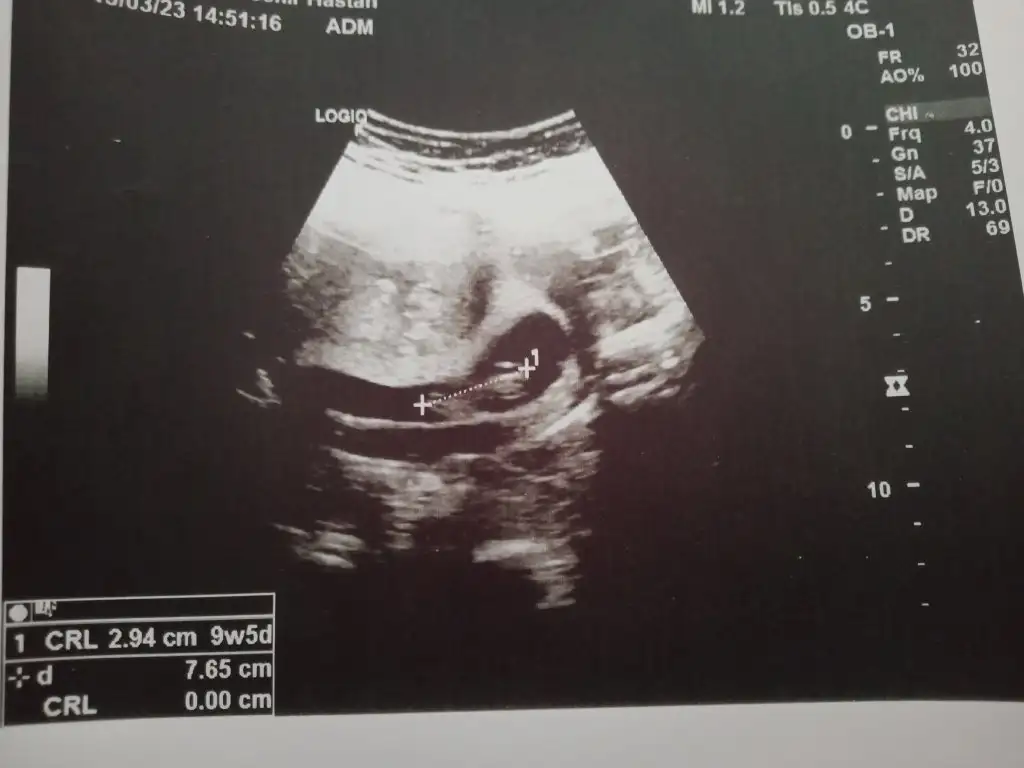

baska varmı ultrason 6-7 haftalık :)Dün kontrolüm vardı kızlar 9+6 olduk bugün nasipse cinsiyet tahmini bekliyorum